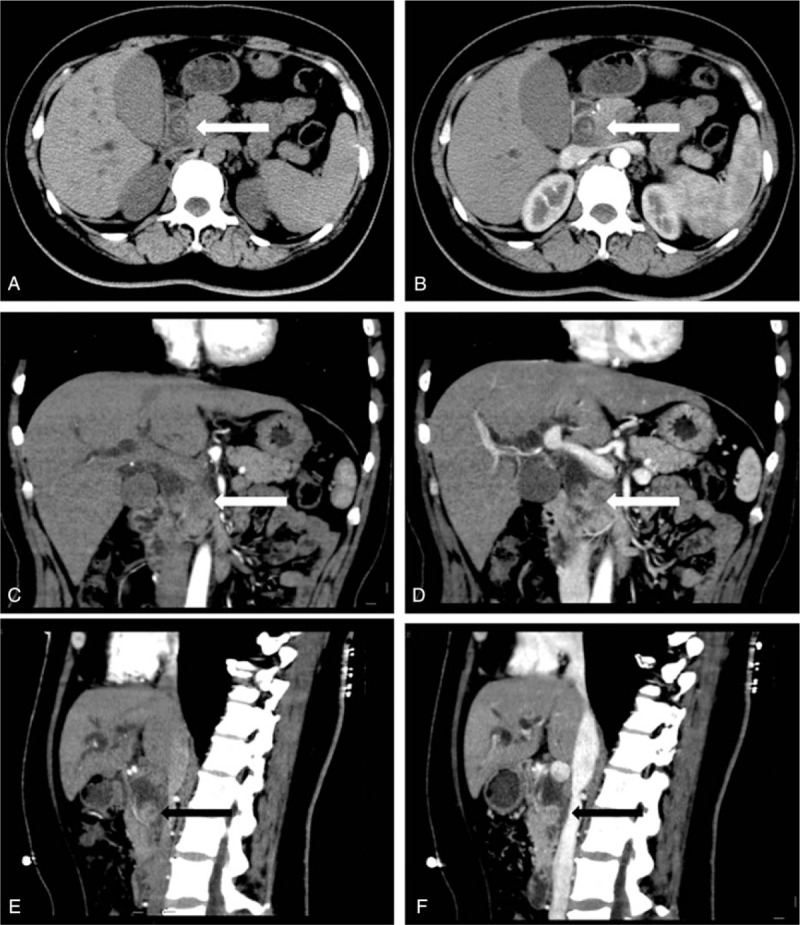

The endoscopic ultrasonography and abdominal computed tomography scans prior to surgery displayed a mass measuring 4.0 × 3.5 cm located in the distal CBD, which had penetrated from the bile duct to the pancreas, with the presence of marked dilatation of the proximal CBD, gallbladder, and right and left common hepatic and intrahepatic ducts (Figs. 1 and 2). No lymphadenopathy was noted in the upper abdomen.